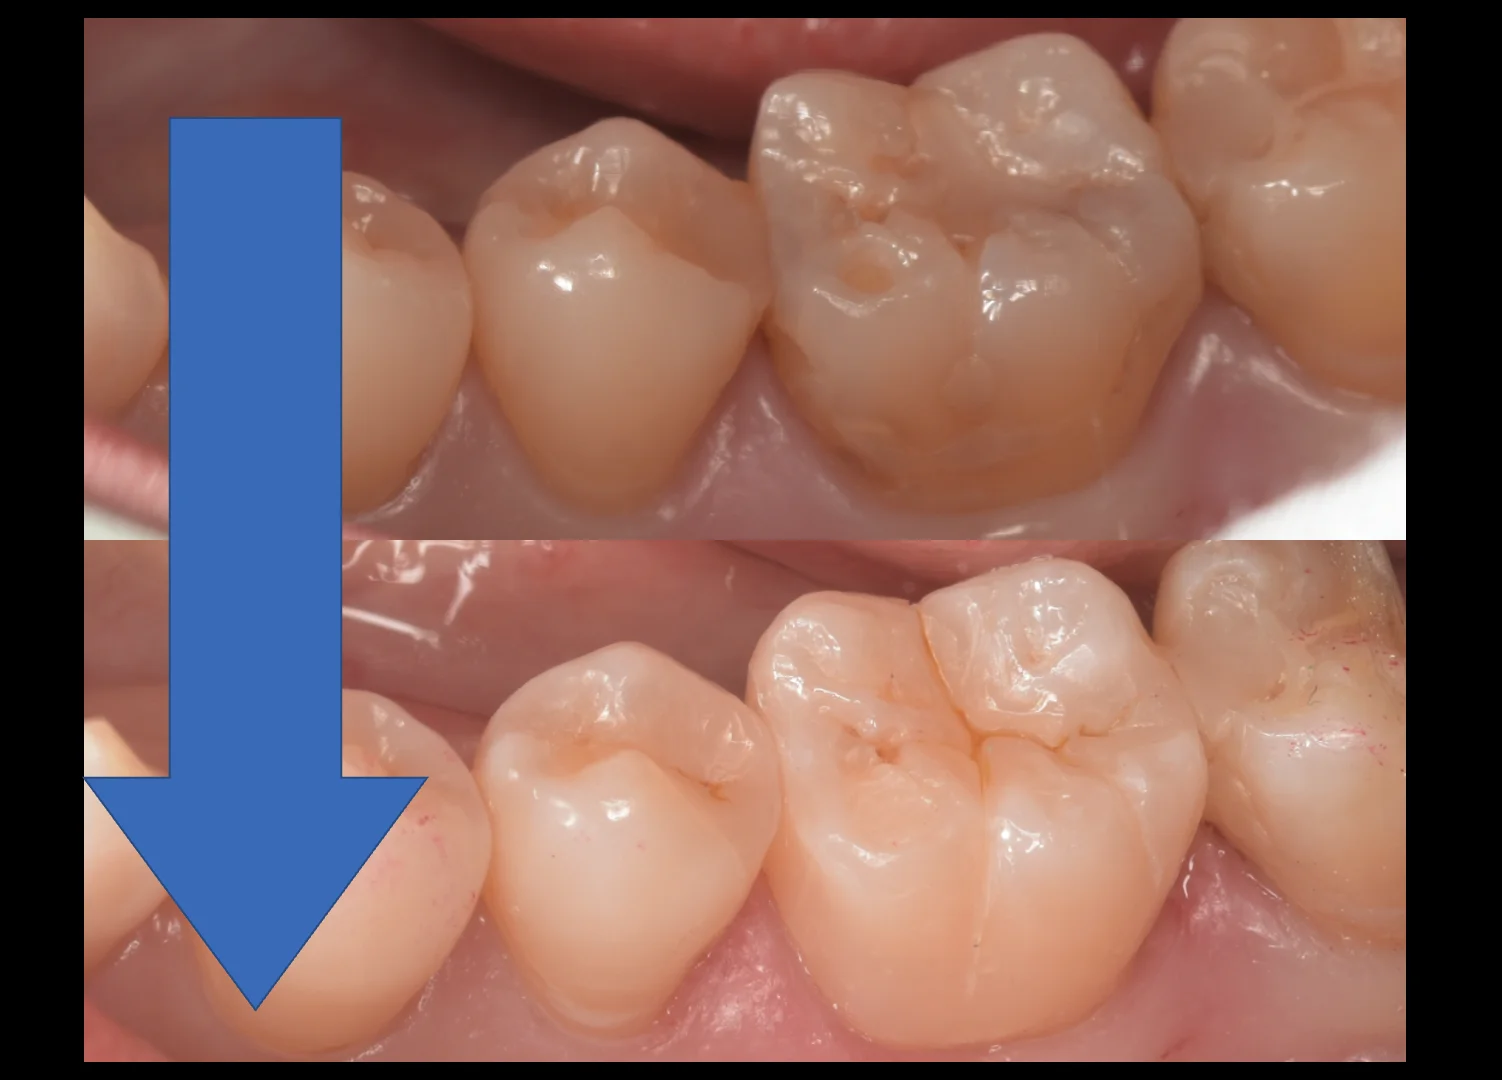

では症例写真に移ります。

まずは術前からです。

上が真上からのアングル・下が側面からのアングルで撮影を行なっています。

というのも、この歯ですが、上下左右全ての面に継ぎ接ぎ状に治療がされており、その接合部分から内部に虫歯ができているような状態だったんです。

なので側面からも併せて撮ることで状況がよりわかりやすくなりそうだったので今回はそういう方向で撮影することにしました。

では、術前術後の比較です。